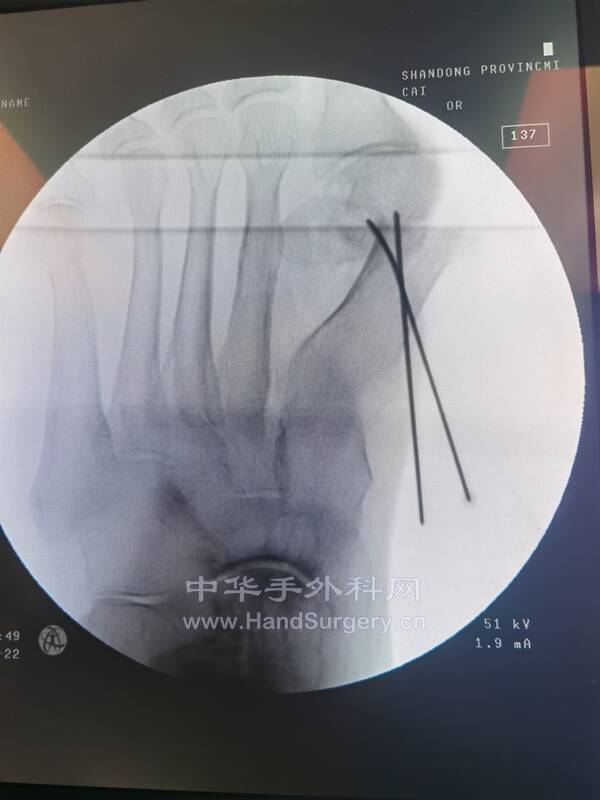

今日参与手术2台注意事项:

2.第一跖趾关节炎:(女性,73岁,有28年跳交际舞史)

踇长伸肌腱背内侧切口,摆锯处理关节面及骨赘,拇趾从中立位我(书上说矫正到轻度旋后位,老师说在临床上效果不好),趾甲与其他趾甲平齐,在拇趾跖内侧置入克氏针1枚,向上推挤确认拇趾最终位置(背伸20-25℃),放入10孔钛板及螺钉内固定,去除克氏针。